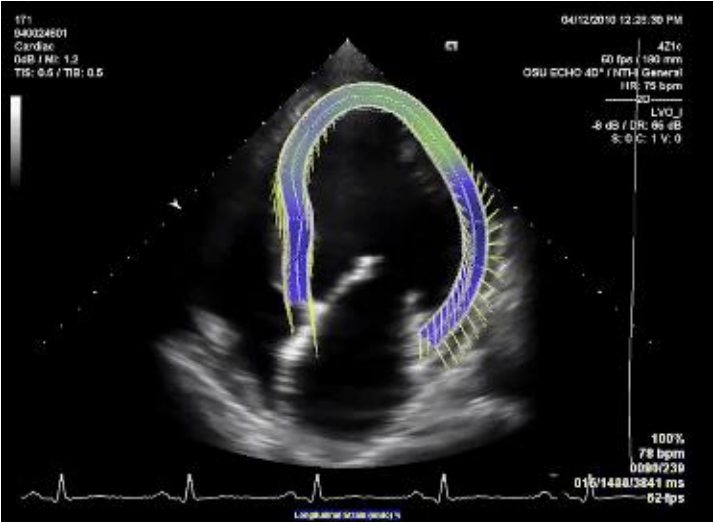

O processamento de vídeo que se pode fazer com estes sistemas de imagem depende muito das capacidades do sistema e das aplicações clínicas (eg. Ecocardiografia)

Interface que permita de forma amigável a gestão do processo de aquisição e apresentação de resultados de quantificação do movimento. Apresentação de histogramas em função das variáveis direção e quantificação do movimento.